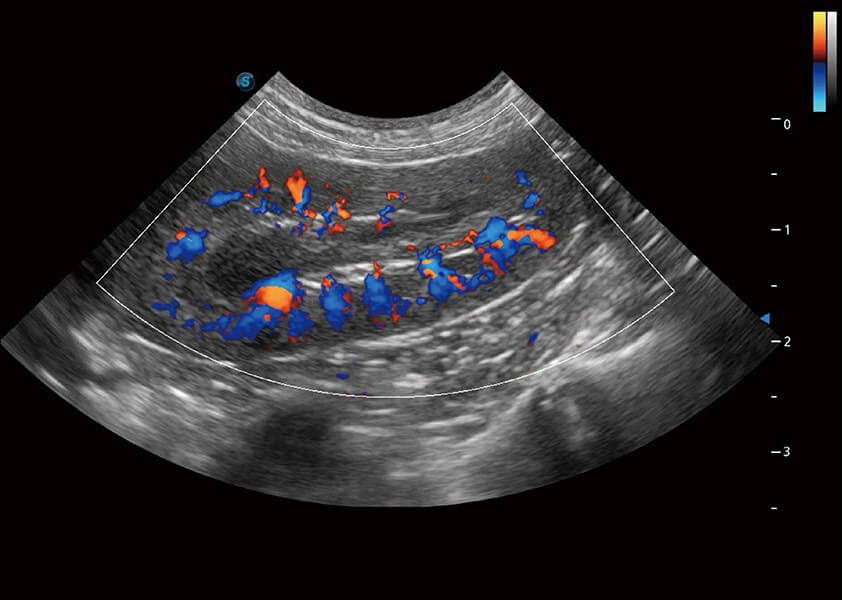

ProPet 60 作为一款高端台式动物超声设备,为动物医生的日常诊断提供了一系列贴合动物临床需求、解决临床实际问题的高级成像功能。凭借全系列高清探头,满足医生对腹部、心脏、生殖、浅表、肌骨等成像的所有需求,切实帮助您提升检查效率,提高诊断信心。

动物是人类最亲密的朋友和最值得信赖的伙伴。环球UG官网也一直致力于探索动物专用的超声影像解决方案。 全新推出的ProPet系列,是环球UG官网在动物超声影像智能化、专业化、精准化的一次跨越式革新。动物不能用言语来表述自己的不适,通过超声影像,ProPet系列搭建了动物医生与不同物种沟通的“桥梁”,为动物医生注入了“治愈之力”。